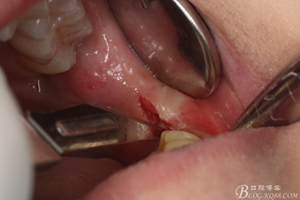

圖6.麻醉效果確定后,在37的近中做垂直松弛切口+遠中水平切口

圖7. 遠中的水平切口